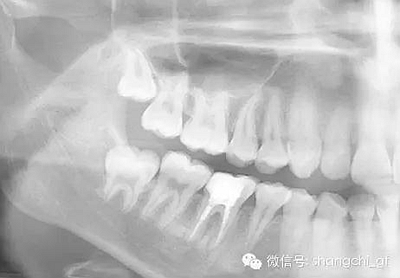

1.拍一張需要去除纖維樁的牙齒的X光片,仔細估算樁的長度,直徑。

手術(shù)前

手術(shù)后